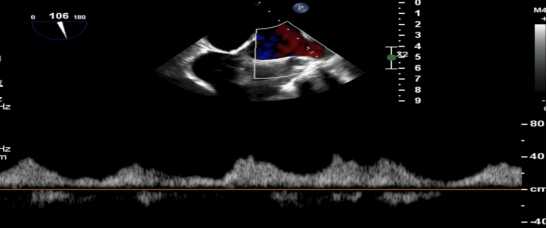

手术当日,在全身麻醉及TEE全程导航下,陈玺全副主任团队凭借丰富的临床经验与精湛操作技巧,顺利完成房间隔穿刺、瓣叶精准定位等关键步骤。针对患者二尖瓣A2/P2 区域反流靶点,团队精准夹合瓣叶,经X-plane技术与三维超声反复确认夹持质量后,成功释放一枚MitraClip XTR夹子。术后即时评估显示,患者二尖瓣反流由术前3 +重度降至轻度,平均跨瓣压仅3mmHg,手术达到预期效果,全程无并发症发生。

术前MR反流